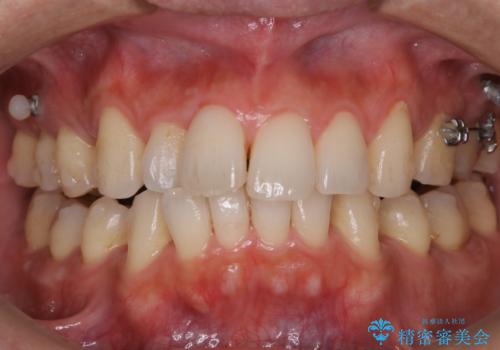

エアーフロー+オフィスホワイトニング

- 3カ月に1度、メンテナンスとしてエアーフローとオフィスホワイトニング来院されてます。

スペシャルコースのオフィスホワイトニングをされていますが、初めの1回はエクセレントコースをされてます。

エアーフロー後のオフィスホワイトニング

エアーフロー後のホワイトニングは、バイオフィルムやぬめりがなく、ホワイトニング剤が吸収しやすく、セットで行うことをおすすめします。